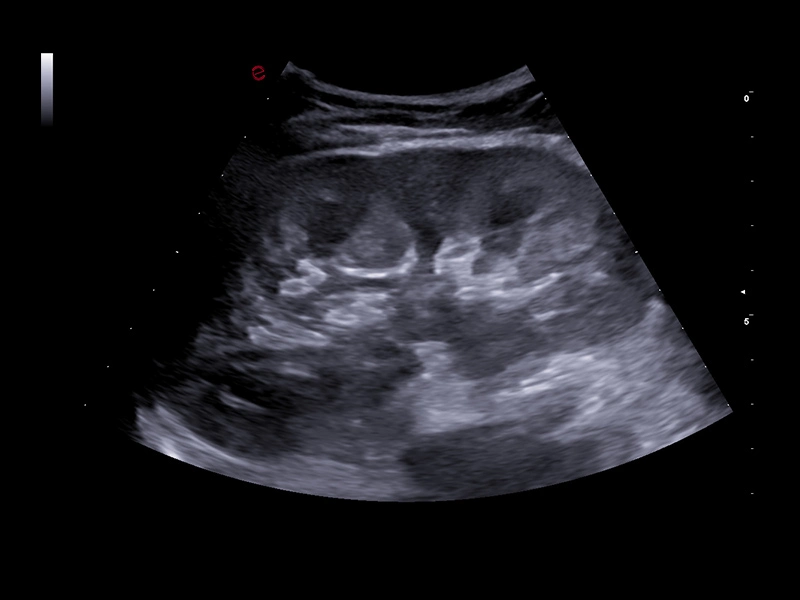

MyLab™C30 - Interventional B-Mode - Testis

MyLab™C30 - Interventional B-Mode - Testis